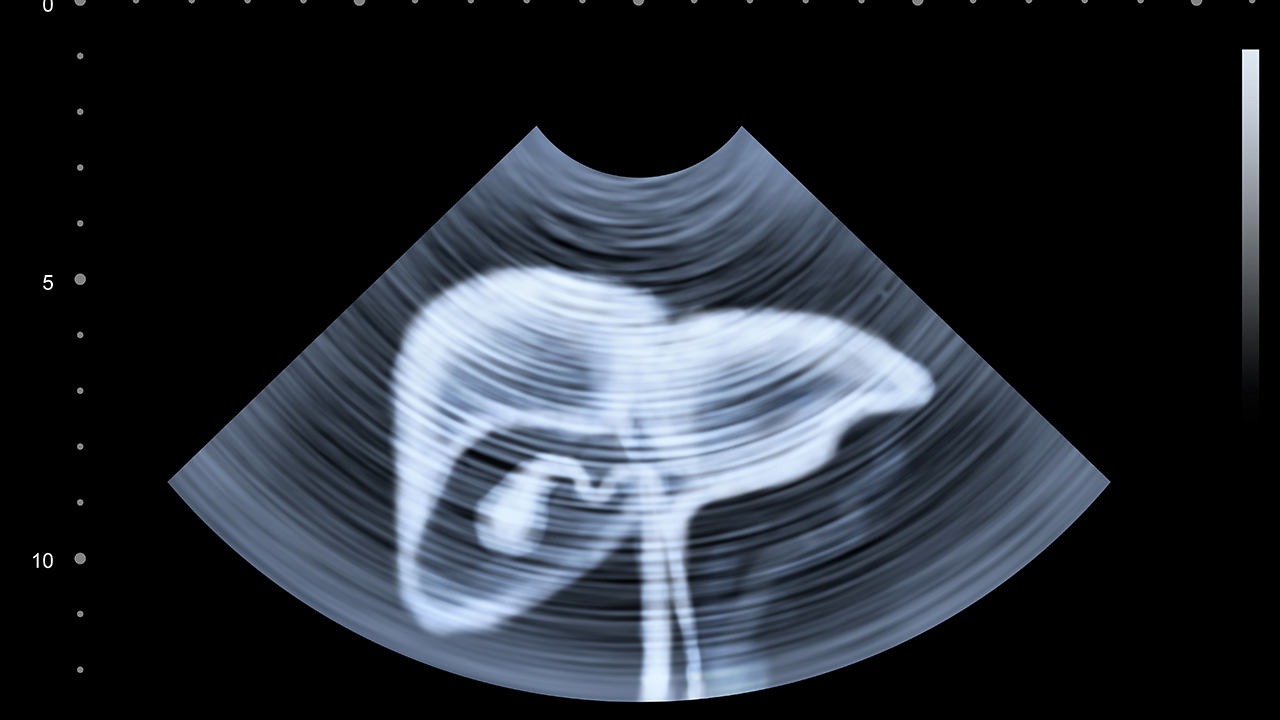

3、穿刺抽液:如果腹水量比较多,并且通过口服药物效果不佳,则需要在医生操作下使用针头将腹水抽出体外,从而减轻腹部压力。但要注意避免一次性抽取过多,以免导致机体出现不适症状。